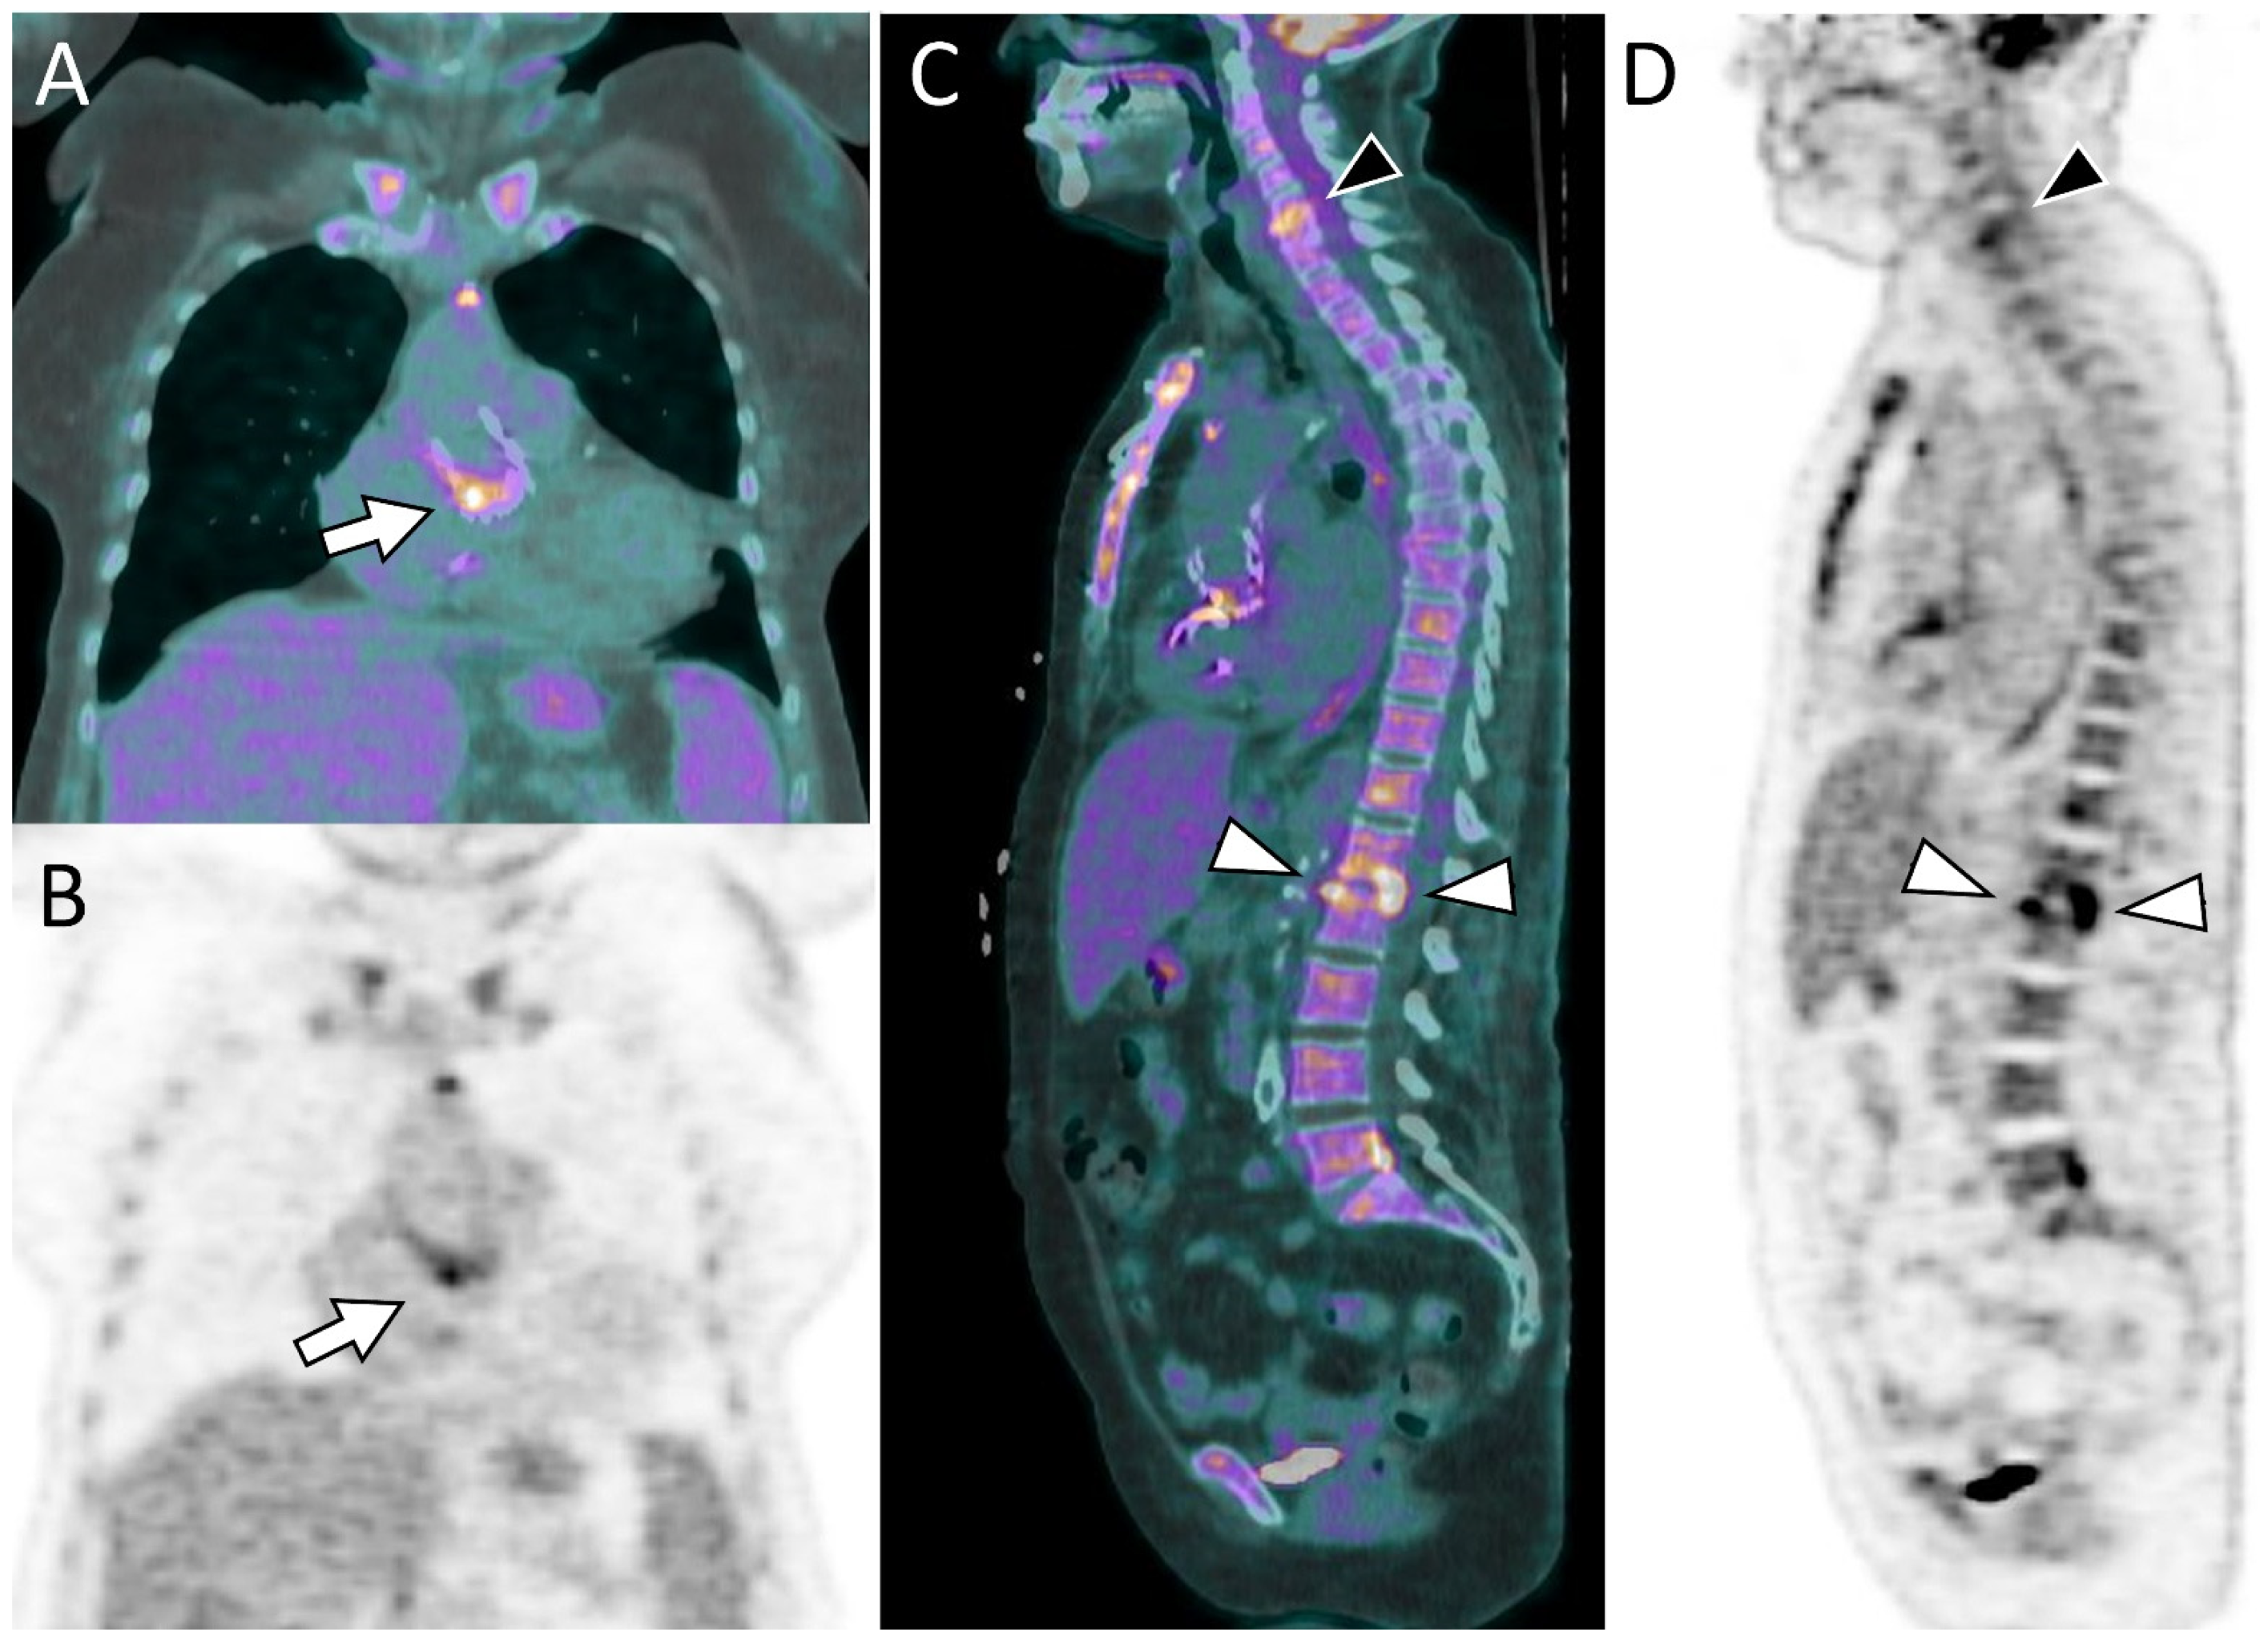

Since Perceval valve implantation is usually selected for patients at moderate to high surgical risk, particularly elderly patients [48], some individuals with Perceval valve endocarditis may be considered poor candidates for cardiac surgery and managed with long-term antibiotic therapy. In this context, PET/CT findings can support clinical decision-making and may be used to monitor the response to antimicrobial treatment [48]. Figure 2 highlights the importance of a comprehensive CT assessment, whereas Figure 3 presents a case of endocarditis with spondylodiscitis, illustrating the value of PET/CT in a patient with inconclusive echocardiographic findings.

Figure 3. A 76-year-old woman with a Perceval prosthetic aortic valve and positive blood cultures for Enterococcus faecalis. Echocardiography revealed a small mobile structure that was inconclusive for vegetation, prompting further evaluation with [18F]FDG PET/CT. Fused (A) and attenuation-corrected (B) coronal images demonstrate focal and intense FDG uptake at the level of the Perceval prosthesis (arrows), consistent with prosthetic valve endocarditis. (C,D) Whole-body imaging additionally revealed findings consistent with spondylodiscitis at the L1–L2 (white arrowheads) and C5–C6 (black arrowhead) levels.